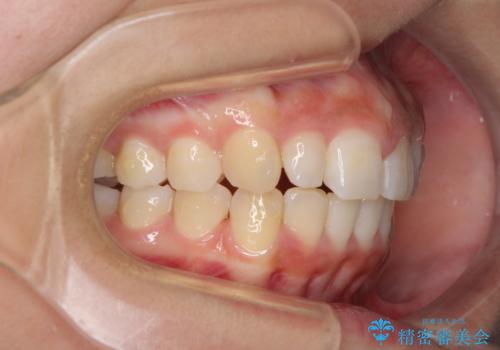

前歯のデコボコを治したい インビザラインによる矯正治療

- 前歯のデコボコ気になるとのことで来院された患者様です。

上下顎ともに歯列全体の後方移動とIPR(歯と歯の間を削る)によってデコボコが解消するように設計し、インビザラインにより治療を行うこととしました。

上顎左右前歯に矮小歯があるため、上顎の奥歯は下顎に対して相対的に前方に位置することになりました。

それでも奥歯の咬みにくさはなく、患者様には大変満足していただきました。